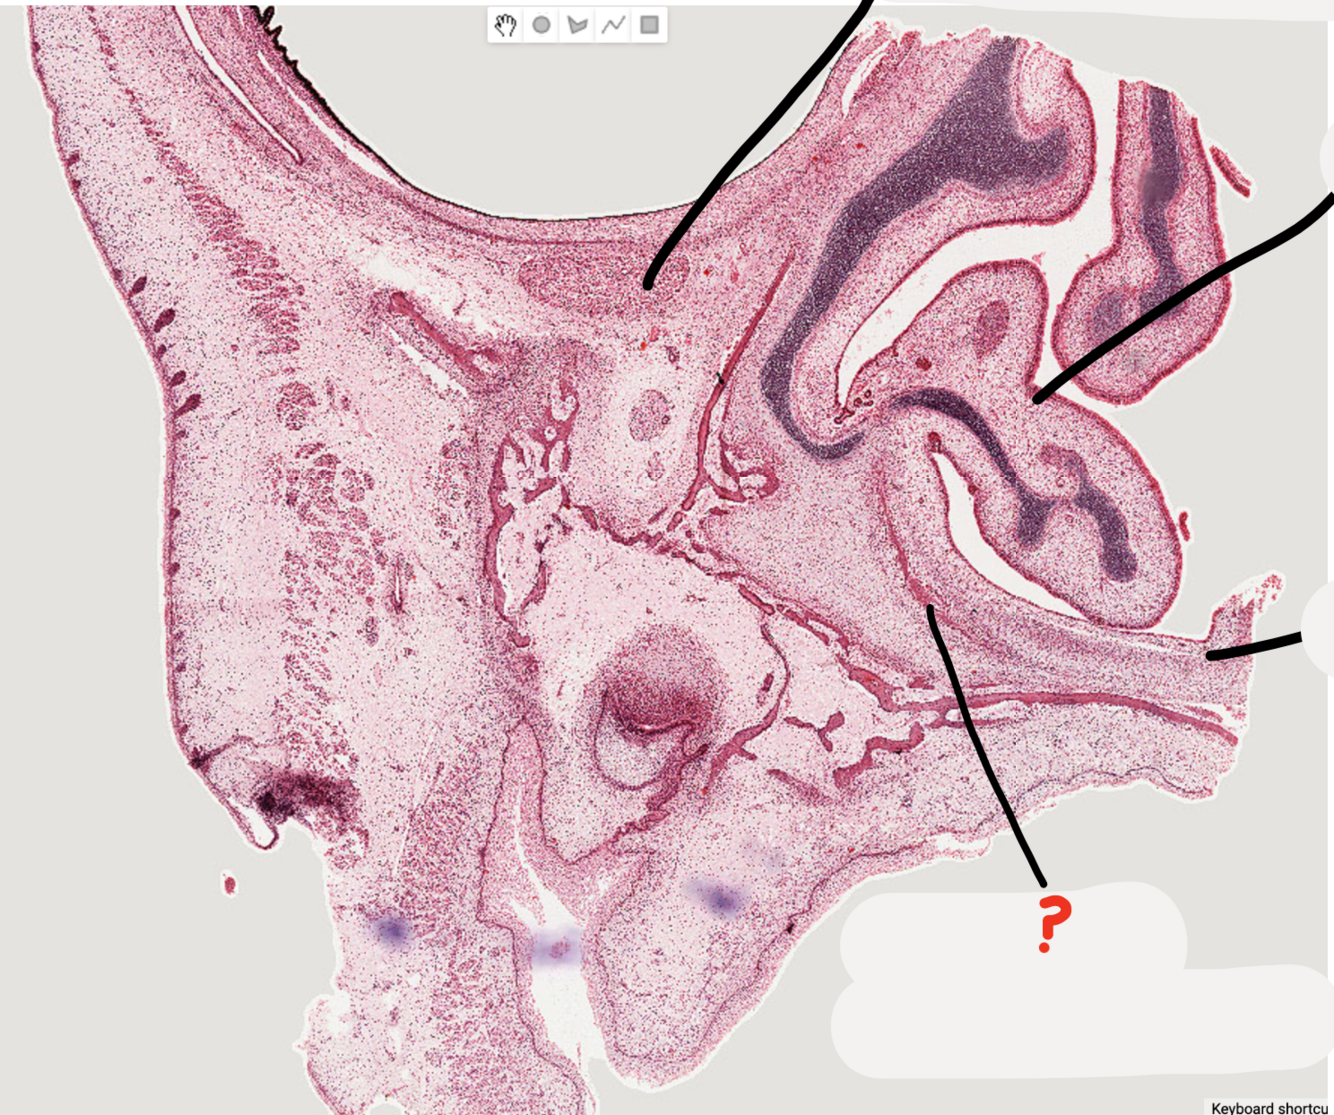

8

Q

what stage of tooth development is this tooth germ?

A

cap stage